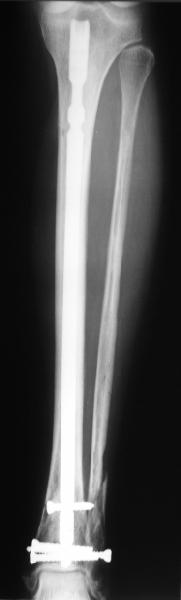

Сделали все-таки стержнем. На всякий случай просверлил дополнительное проксимальное отверстие, так что получилось три 45-градусных винта.

В дистракторе провеи спиц поболше в прокисмальном отделе, чтобы не разобщить фрагменты при сгибании колена. Комментарии и критика приветствуются.

We proceeded with nailing using a small wire distractor, with few wires at the proximal end to prevent displacement with forced knee flexion. Images attached. Comments and critics are welcome.

It is often a problem nailing upper tibial fractures. There is a tendency to apex anterior angulation as well as valgus alignment. Your entry point on the AP view seems to have been kept the same. How did you manage to maintain alignment? Any intra-operative pictures of your technique?

The lateral view shows your entry point to be quite posterior and I think this is recommended to avoid anterior angulation. Were you concerned about intra-articular penetration?

Overall an excellent post-op x-ray. Well done.